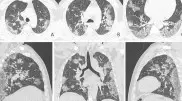

"Матовое стекло". Как развивается пневмония у инфицированных COVID-19 Icon "Матовое стекло". Как развивается пневмония у инфицированных COVID-19 Telegram-канал Baza опубиковал материал, в котором просто и понятно описал, как именно у инфицированных COVID-19 развивается пневмония

Ученые показали видео, как коронавирус поражает легкие Icon Ученые показали видео, как коронавирус поражает легкие Американские доктора из университета Джорджа Вашингтона использовали технологию виртуальной реальности, чтобы показать, как коронавирус поражает